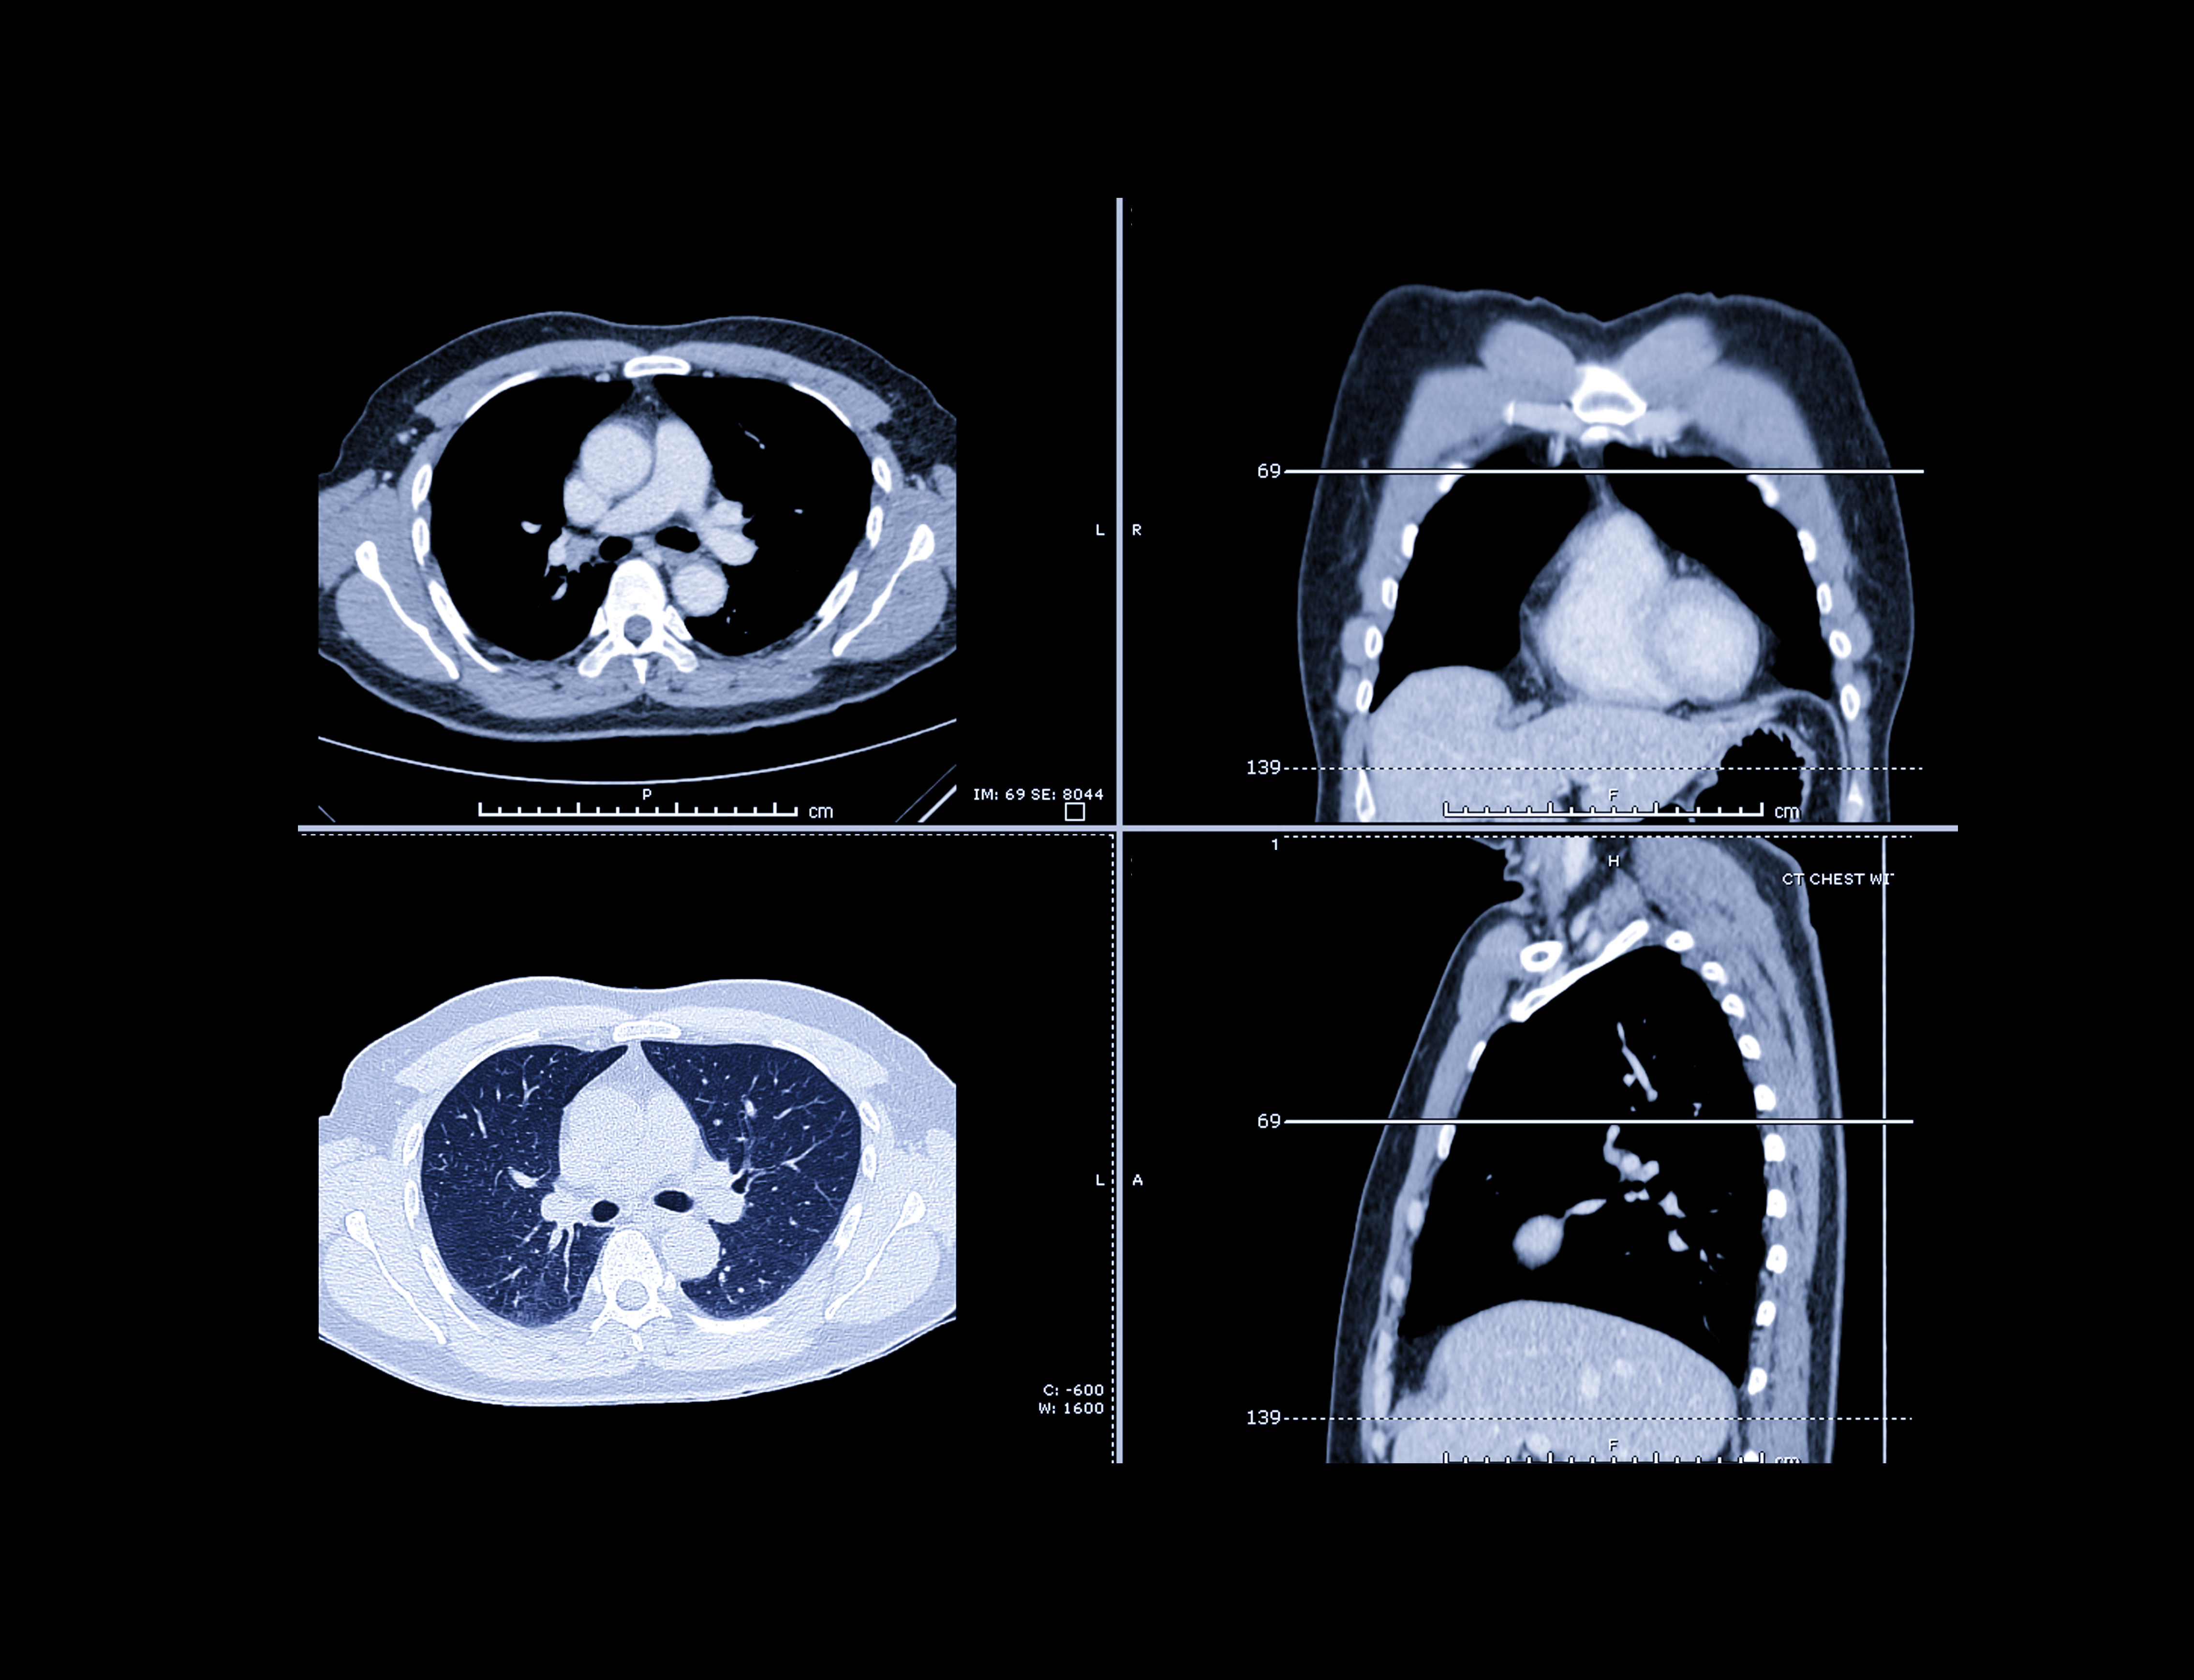

For Brainomix's part, the substudy featuring e-Lung will run alongside the main study. The platform is an AI-powered image processing module and tool that standardizes the quantification of lung fibrosis on high-resolution CT scans to identify progressive fibrosis patients.

Helping with this is a novel imaging biomarker, the weighted reticulovascular (WRV) score. This quantifies the extent of the lung affected by reticulovascular abnormalities. The company wants to find out the difference in WRV score change between baseline and 12 months postrandomization between treatment with lansoprazole and a placebo.